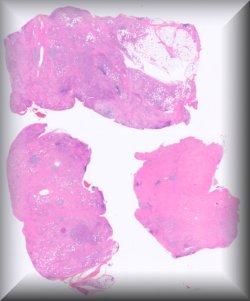

María Miguelina de la Garza Bravo (Houston): 53-year-old male with a 10-year-old history of bilateral exophthalmos (R>L), status post debulking. |

|